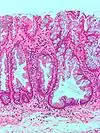

| Type de polype | Apparence histologique | Risque de malignité | Coupe histologique | Syndromes | |

|---|---|---|---|---|---|

| Hyperplasique | Cryptes dentées non-ramifiées | Non |  | Hyperplasique polypose syndrome | |

| Adénome dentelé sessile | Semblable à hyperplasique avec hyperserration, bases des cryptes dilatées/ramifiées, des cellules de mucine apparents à la base des cryptes | Oui |  | ||

| Inflammatoire | Muqueuse/sous-muqueuse élevées avec inflammation | Si développement d'une dysplasie | Maladies inflammatoires chroniques intestinales, ulcères, infections, prolapsus muqueux | ||

| Adénome tubulaire (villositaire, tubulovilleux) | Glandes tubulaires avec des noyaux allongés (au moins à faible teneur atypie) | Oui |  | ||

| Adénome dentelé traditionnel | Cryptes dentelées, souvent une structure villeuse, avec atypie cytologique, des cellules éosinophiles | Oui |  | ||

| Polype de Peutz-Jeghers | Faisceaux musculaires lisses entre l'épithélium non-néoplasique, apparence d'« arbre de Noël » | Non |  | Syndrome de Peutz-Jeghers | |

| Polype juvénile | Glandes kystiques dilatées avec la lamina propria élargie | Non intrinsèquement, peut développer une dysplasie |  | Syndrome de polypose juvénile, polypes identiques que dans le syndrome de Cronkhite-Canada | |

| Polype hamartomateux | Variable ; polype classique légèrement fibreux avec la muqueuse désorganisée et écartement des muscularis mucosae ; aussi inflammatoire, juvénile, lipome, ganglioneurome, lymphoïde | Non | Maladie de Cowden | ||

| Polype fibroïde inflammatoire | Cellules en fuseau avec des amas concentriques de cellules fusiformes autour des vaisseaux sanguins et l'inflammation riche en éosinophiles | Non |  | ||